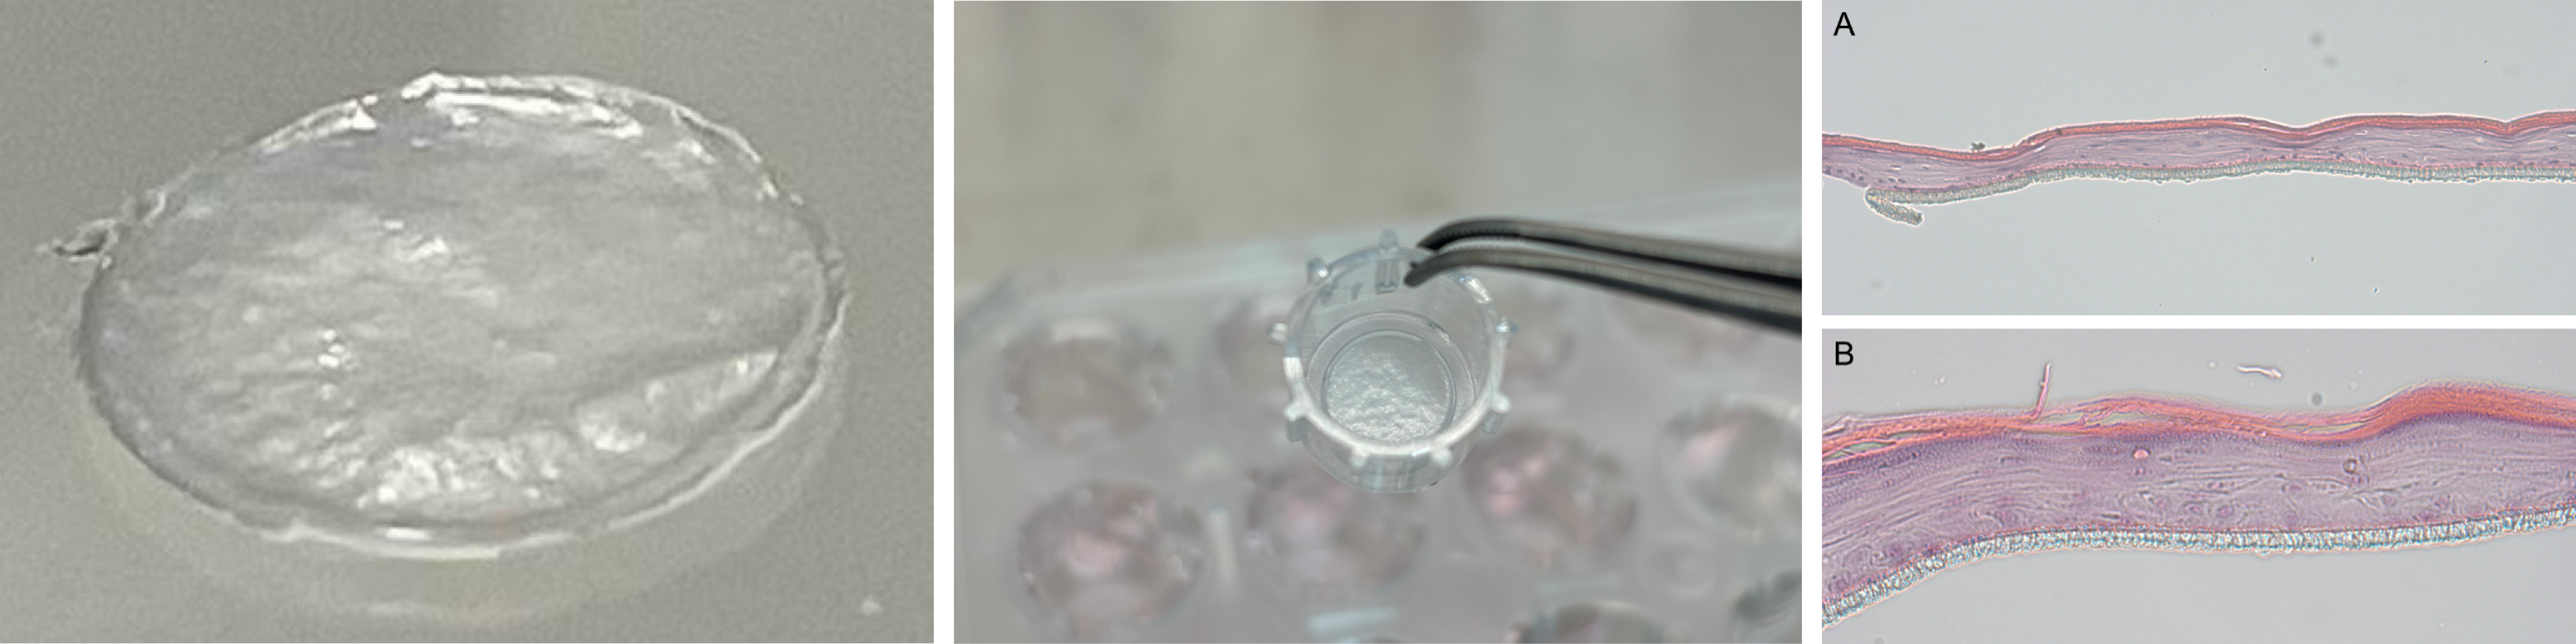

By improving the culturing method, Pigeon successfully created an artificial skin model that included the stratum corneum, which has the skin barrier function, within 24 days, which is faster than usual. (Fig. 1A)

Construction and evaluation of infant skin model using iPSC-derived keratinocytes (iPSC-KCs)

Fig. 1. (A) Gene expression in iPSC-derived RHE and RHE, (B) HE chromosome results and Filaggrin/AQP3, (C) Immunofluorescence staining results